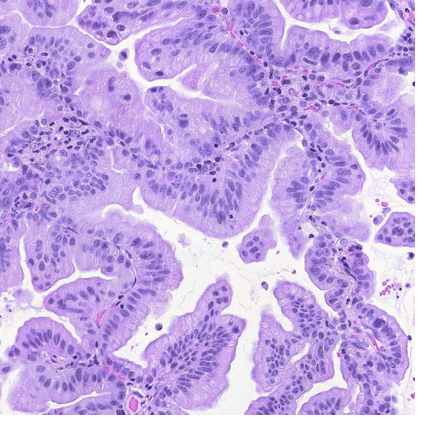

Significantly enlarged and hyperchromatic nuclei with increased nuclear-to-cytoplasmic ratio, irregular nuclear membranes, and nuclear crowding suggest high-grade atypia consistent with typical cancer cell cytology — a key region for tumor characterization.

Under high magnification, tumor cell nuclei are significantly enlarged and hyperchromatic with clearly visible nucleoli. Intracytoplasmic mucin vacuoles of varying sizes suggest adenocarcinoma features. No intercellular bridges or keratinization observed.